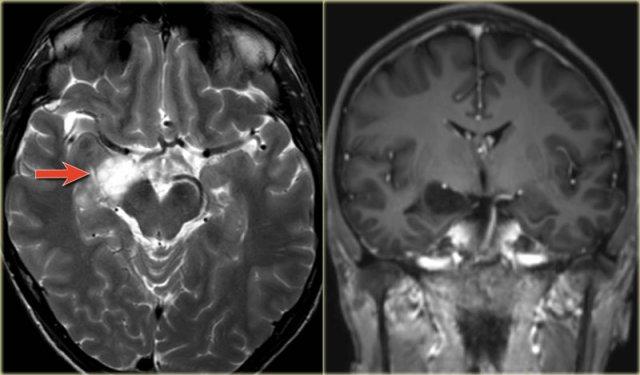

Các hình ảnh cho thấy loạn sản vỏ não khu trú điển hình.

Có hình ảnh dày vỏ não và mờ ranh giới chất xám/chất trắng trên chuỗi xung T1W (bên trái).

Ảnh FLAIR bên phải cho thấy tăng tín hiệu vùng dưới vỏ.

Các hình ảnh cho thấy bất thường tín hiệu vỏ não và dưới vỏ trên chuỗi xung T2W và FLAIR ở thùy thái dương trái, phù hợp với loạn sản vỏ não khu trú.

Lưu ý hình ảnh hồi hải mã tăng tín hiệu T2/FLAIR kèm teo nhỏ là hậu quả của xơ cứng thùy thái dương giữa, tức là bệnh lý kép.